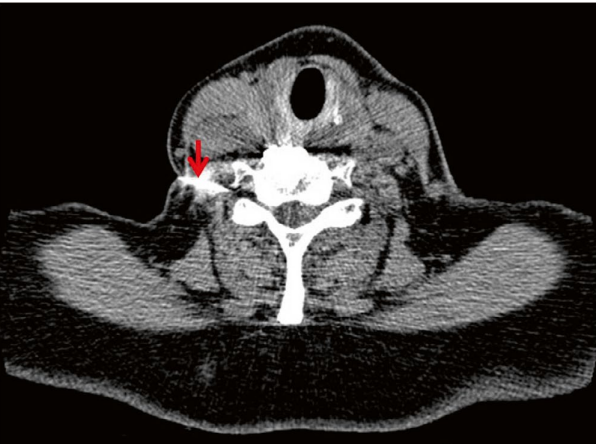

顽固性疼痛或肌无力可考虑CT引导下经椎间孔神经根注射(图2)。局麻药(如利多卡因)可暂时阻断疼痛信号,糖皮质激素(如曲安奈德)需注意超说明书使用风险。

图2:CT引导下颈椎神经根阻滞术(红色箭头:穿刺针位置)